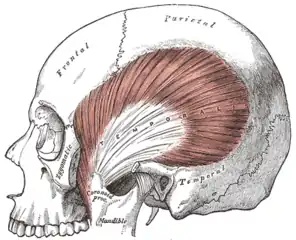

Muscles of mastication

The muscles of mastication are paired on each side and work together to produce the movements of the mandible. The main muscles involved are the masseter, temporalis and medial and lateral pterygoid muscles.

Left medial and lateral pterygoid muscles

Left medial and lateral pterygoid muscles Left temporalis muscle

Left temporalis muscle.png.webp) Left masseter muscle (red highlight)

Left masseter muscle (red highlight)

They can be thought of in terms of the directions they move the mandible, with most being involved in more than one type of movement due to the variation in the orientation of muscle fibers within some of these muscles.

- Protrusion – Lateral and medial pterygoid.

- Retraction – Posterior fibers of temporalis (and the digastric and geniohyoid muscles to a lesser extent).

- Elevation – Anterior and middle fibers of temporalis, the superficial and deep fibers of masseter and the medial pterygoid.[42]

- Lateral movements – Medial and lateral pterygoid (the ipsilateral temporalis and the pterygoid muscles of the contralateral side pull the mandible to the ipsilateral side).[35]

Each lateral pterygoid muscle is composed of 2 heads, the upper or superior head and the lower or inferior head. The lower head originates from the lateral surface of the lateral pterygoid plate and inserts at a depression on the neck of mandibular condyle, just below the articular surface, termed the pterygoid fovea. The upper head originates from the infratemporal surface and the infratemporal crest of the greater wing of the sphenoid bone. The upper head also inserts at the fovea, but a part may be attached directly to the joint capsule and to the anterior and medial borders of the articular disc.[42] The 2 parts of lateral pterygoid have different actions. The lower head contracts during mouth opening, and the upper head contracts during mouth closing. The function of the lower head is to steady the articular disc as it moves back with the condyle into the articular fossa. It is relaxed during mouth closure.[26]